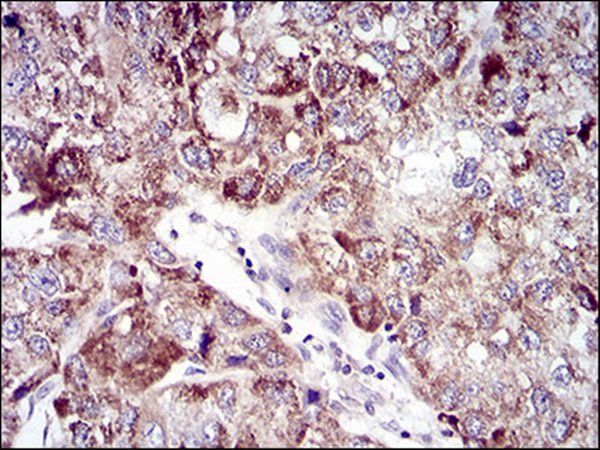

Immunohistochemical analysis of UBE2C staining in human colon cancer formalin fixed paraffin embedded tissue section. The section was pre-treated using heat mediated antigen retrieval with sodium citrate buffer (pH 6.0). The section was then incubated with the antibody at room temperature and detected using an HRP conjugated compact polymer system. DAB was used as the chromogen. The section was then counterstained with haematoxylin and mounted with DPX.